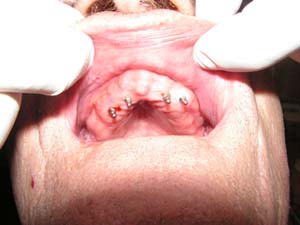

The Procedure

In the procedure titanium screws (implants) with integrated ball-tops are inserted into the jaw, where they will fuse into the bone. The procedure typically takes about an hour, and can be done under local anesthesia. Your existing denture is modified to sit comfortably over the implants during the healing phase. After the implants have healed, your denture is modified to snap onto the ball-tops. The denture will be secure until you remove it for cleaning. Simply apply upward pressure to the front of the denture with your thumbs to unseat the denture.